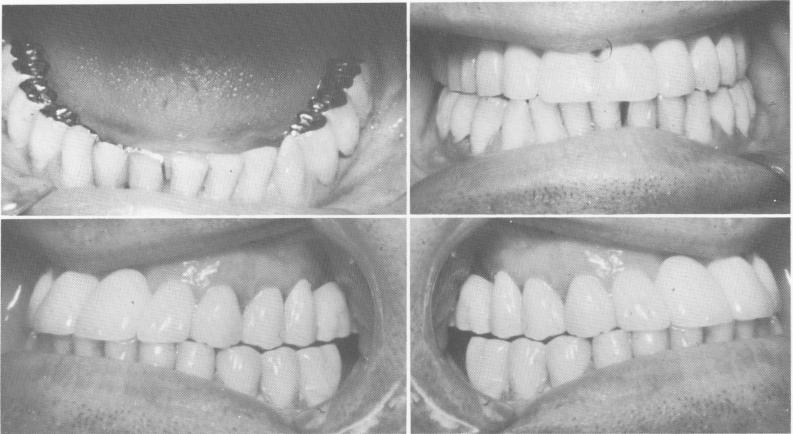

Fig. 15-31. A severe cross bite relationship.

both jaws at rest. This does not necessarily mean in-creasing the vertical dimension. An illustrative case is shown beginning with Fig. 15-31. The patient had previously undergone bite-raising procedures that opened his bite with removable appliances but that caused great discomfort and pain in his temporomandibular joints. His preoperative Panorex revealed very few maxillary teeth (Fig. 15-32) .

Using the patient's removable denture as a plat-form, the operator molded a thick mix of acrylic over the denture and over the existing prepared teeth while the patient's jaw was in the most retruded position. It was imperative to maintain as close a bite as possible during this procedure in order not to increase the patient's true vertical dimension. Thus the bite was opened just enough to allow the molded max-

illary acrylic teeth to come edge to edge with the mandibular incisors. Once this had been accomplished, the temporary teeth were trimmed and polished. The physiologic rest position was immediately checked. If no rest position existed, it would have been necessary to shorten the acrylic teeth.

The patient wore the provisional splint for about 4 weeks, with no pain or discomfort. Using the "built-up" acrylic teeth on the removable denture as a bite guide, the operator fabricated impressions and castings for the teeth on the right side of the arch (Fig. 15-33). Blade implants were then placed on both sides of the maxillary arch (Fig. 15-34). All remaining mandibular teeth were prepared, and blade implants were placed in both posterior endentulous areas (Fig. 15-35).

A full arch fixed porcelain-baked-to-metal pros-thesis was completed for each arch, placing the jaws in a Class I relationship (Fig. 15-36) . A Panorex of the completed case shows the blade implant supports (Fig. 15-37).